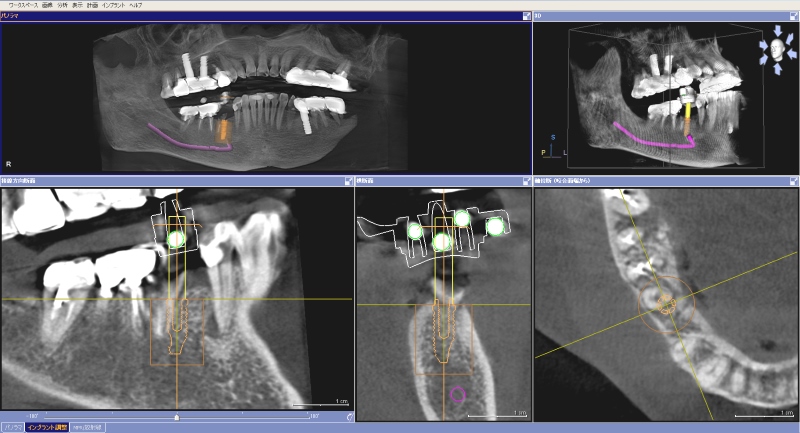

シュミレーションしたCT画像

3D画像で360°様々な方向から立体的に顎の骨を観ることができ、その画像を元にシュミレーションができます。

また、専用ソフトで作製したコンピューターガイドを使用することにより、確実で安全なインプラント治療の実現が可能になりました。